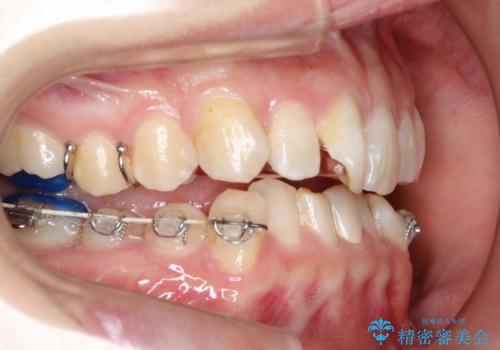

ハーフリンガル ワイヤー矯正による非抜歯・過蓋咬合の治療

- 非抜歯、大臼歯遠心移動による臼歯関係の是正・過蓋の改善をハーフリンガル・ワイヤー矯正にて計画した。